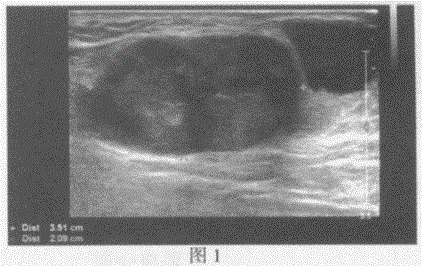

问题 临床资料:女,70岁,自诉确诊左足底恶性黑色素瘤两年余,中药治疗无明显好转来诊。 超声综合描述:左腹股沟区可见多个低回声(图1),部分相互融合,最大3.5cm×2.1cm,边界清晰,形态不规则,内回声不均,CDFI:内可见血流信号。左腹股沟区另可见多个不均质回声区(图2),最大2.1cm×1.8cm,边界清晰,形态不规则,内可见无回声区,CDFI:不均质回声区内可见血流信号。 超声提示: